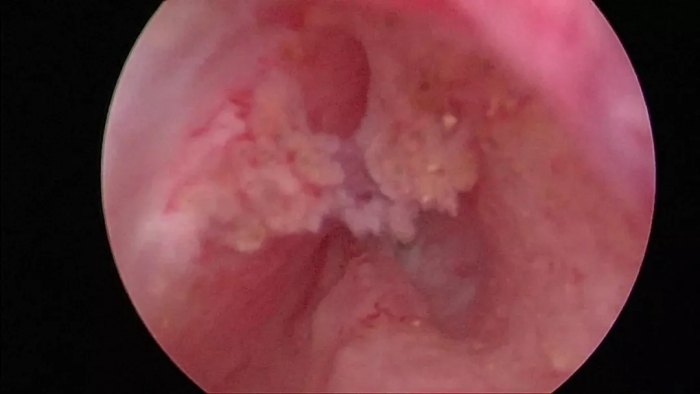

(术前堵塞)

(术后通畅)

“前列腺等离子微创电切”PKRP系统具有独特的靶组织识别功能,当电切环与包膜接触时,能量自动变小,切割停止,从而保护了包膜,降低了腔内电切的难度及手术的风险。

④ 术中止血效果好,术后继发性出血少。

传统前列腺电切术或前列腺气化电切术通过直接接触组织产生高温使周围组织凝固坏死,凝固层厚度较薄,止血效果差,恢复期凝固坏死组织可易脱落,导致继发性出血。“前列腺等离子微创电切术”切割时在组织表面形成lmm左右深的均匀凝固层,术中止血效果较好,凝固层不会脱落,术后继发性出血几率小。